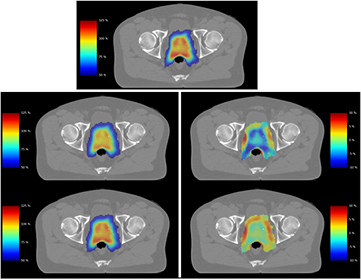

Figure 4 presents the impact of these effects in a clinical prostate radiotherapy plan, planned with zero CTV margin, and a volume equivalent to a target diameter of 48 mm. When compared to physical dose (top), incorporating signalling-driven effects leads to a significant drop in target EUD for 2 Gy fractions (7%, middle), with nearly 20% of the 2 Gy target volume now falling below the prescription dose. However, as fraction size is increased this effect is diminished, and at 8 Gy fractions little impact is seen (bottom, 1%). These differences are highlighted by dose difference plots (right middle & bottom) which show the change in effective dose between signalling-adjusted and physical doses for high-dose voxels (those seeing >50% of the prescription dose). Outside the target, both fraction sizes see significant increases in cell killing in the lower-dose region immediately surrounding the target. More detailed discussion of signalling effects in low-dose regions can be found in previous work (McMahon et al 2013b).

Figure 4. Illustration of reduced signalling in clinical external beam radiotherapy plan. In this VMAT plan, a given physical dose distribution (top) is converted into signalling-adjusted dose for doses of 2 (middle) or 8 (bottom) Gy per fraction. Treatments are illustrated either as effective dose maps (left) or dose difference maps (right) for voxels which see greater than 50% of the prescription dose. A significant drop in target dose is seen compared to the physical case at 2 Gy, while good correspondence is seen at 8 Gy per fraction.

Standard image High-resolution imageSignalling-adjusted EUD analysis was carried out for each of these treatment plans, and is presented in figure 5, normalised to prescription dose as in figure 3. While comparisons between different margin and dosing selections are more difficult due to the increased field complexity needed to deliver treatments with the very smallest margins, the key observations from the simpler model—that the irradiation of tissue outside the target volume or the use of higher doses increases biological effectiveness—remain even in this more complex scenario.

Figure 5. Effects of varying margin and dose per fraction on normalised signalling-adjusted EUD for a patient geometry. As in the idealised case, increases in both fraction size and margin prescription lead to predicted increases in EUD.